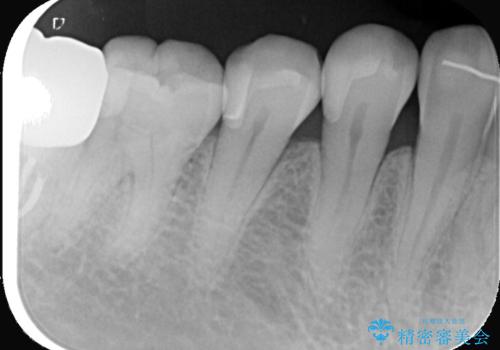

- 右下5の虫歯をセラミックインレーで修復しました。虫歯は進行することで歯に悪影響を及ぼし、放置するとさらなる問題を引き起こす可能性があります。再発のリスクをできるだけ回避するため、セラミックインレーを用いて治療を行いました。